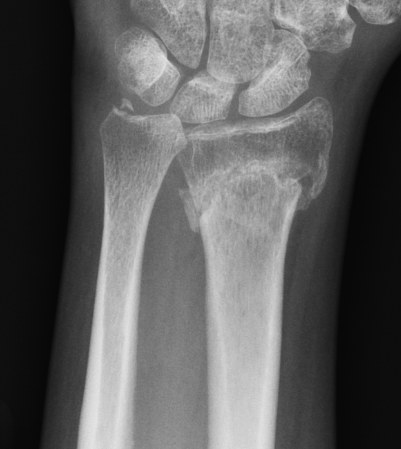

DRUJ instability after distal radius fracture

1. Ulna styloid fracture

Ulna styloid fractures occur in half of all distal radius fractures

Anatomy

Ulna styloid

- bony projection from ulna

- fovea at base for soft tissue attachments

- TFCC / radio-ulna ligaments

Classification ulna styloid fractures

| Type 1: Tip | Type 2: Base | Type 3: Proximal to styloid |